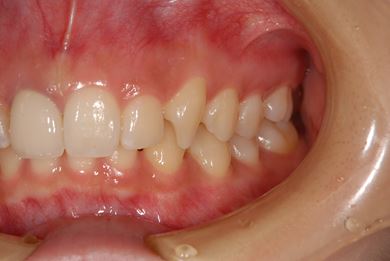

| 性別/年齢 | 女性 / 21歳 | ||||||||||||||||||||||||||||||||

| 主訴 | 歯の変色、欠けた部分を治したい。 | ||||||||||||||||||||||||||||||||

| 治療方針 | 上前歯を根管治療後、オールセラミッククラウンにて審美的回復を行う。 | ||||||||||||||||||||||||||||||||

| 治療内容 | オールセラミッククラウン2本(オールセラミック用土台2本) | ||||||||||||||||||||||||||||||||